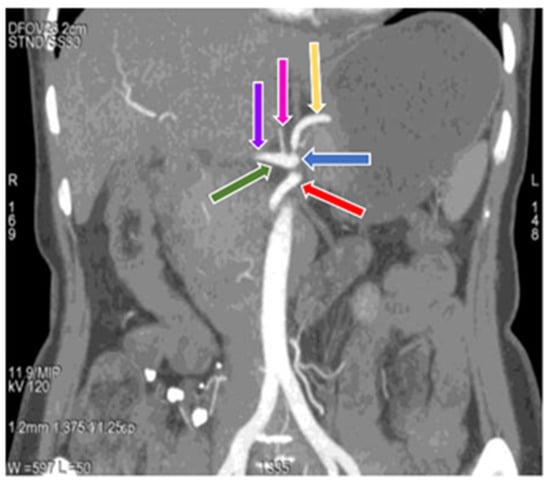

3.1. Variation in Origin and Branching Pattern of Celiac Trunk